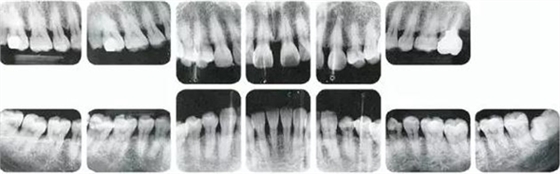

25歲女性。菌斑控制狀態(tài)不好。齦溝除磨牙處外全在3mm以下,X光照片上左上、右下、左下的第一磨牙上有垂直性骨吸收。這個(gè)病例是參考病例①10年前的狀態(tài),是典型的侵襲性牙周炎局部型。

牙周病的發(fā)展因部位不同而發(fā)展程度不同的。10點(diǎn)后的狀態(tài)參考病例①和參考病例②的磨牙處的狀態(tài)相比較,思考下沒(méi)接受治療病情發(fā)展的特別性吧。

參考病例① 35歲女性

在左下第一磨牙在25歲時(shí)近中處可以看到垂直性的骨吸收,但35歲時(shí)吸收停止,原本沒(méi)有見(jiàn)到的遠(yuǎn)中處骨吸收的,現(xiàn)在卻吸收得很?chē)?yán)重。

在右下處,原本有大量骨吸收的第一磨牙處的吸收卻變緩慢,原本沒(méi)有吸收的第二前磨牙卻出現(xiàn)了吸收。出現(xiàn)吸收的左上第一磨牙的遠(yuǎn)中處,吸收得越來(lái)越多了。

把10年間的變化做成表格。牙周病的發(fā)展根據(jù)各個(gè)人會(huì)不同,即使通一個(gè)人,不同牙齒,不同牙面發(fā)展的狀態(tài)也不同。